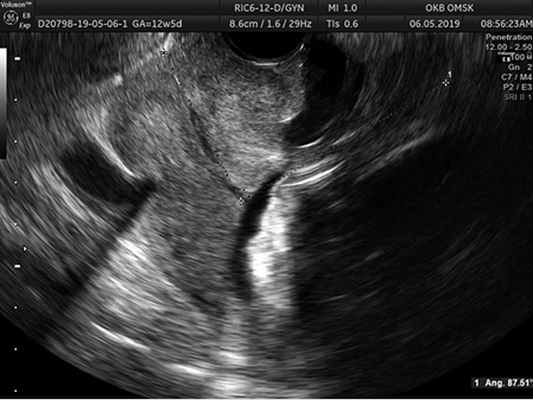

Методы исследования. У всех беременных основной группы и группы сравнения проводили оценку анамнеза, данных клинического исследования, общепринятых лабораторных показателей, результатов ультразвукового исследования (УЗИ), которое выполнялось на аппарате VolusonTME8/E8 Expert, при этом оценивали величину переднего маточно-цервикального угла, проводили цервикометрию, гистологическое и иммуногистохимическое исследование удаленных макропрепаратов.

Методика измерения переднего маточно-цервикального угла состоит в следующем: измерение маточно-цервикального угла начинали с проведения линии А между точками внутреннего и наружного зева цервикального канала. Вторую линию — D проводили вдоль передней стенки нижнего сегмента матки по внутреннему краю и области внутреннего зева шейки матки. За исследуемый принимали угол, обращенный кверху (над шейкой матки). В случае низкого расположения миоматозного узла, когда имелись затруднения в четкой визуализации внутреннего края передней стенки матки, передний маточно-цервикальный угол измеряли по наружному краю передней стенки матки. При этом при измерении по наружному и внутреннему краям разница величины угла не превышала 3—5° (рис. 1).

Рис. 1. Методика измерения переднего маточно-цервикального угла у беременных с миомой матки больших размеров. Фото.